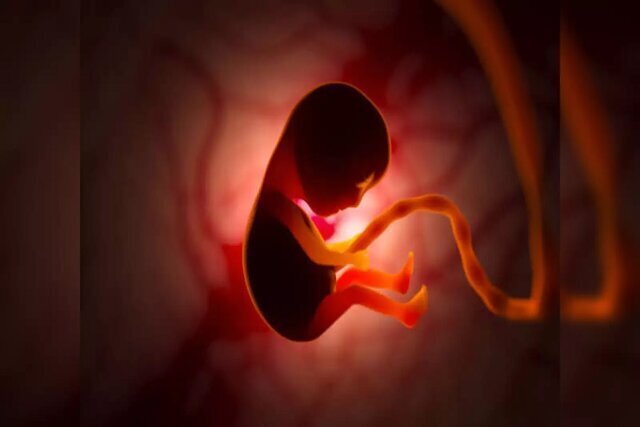

سقط جنین چطور باعث مرگ مادر میشود؟

آفتابنیوز : سالانه بین ۳۵۰ تا ۵۳۰ هزار مورد سقط جنین در ایران انجام میشود که معادل روزانه آن ۱۰۰۰…